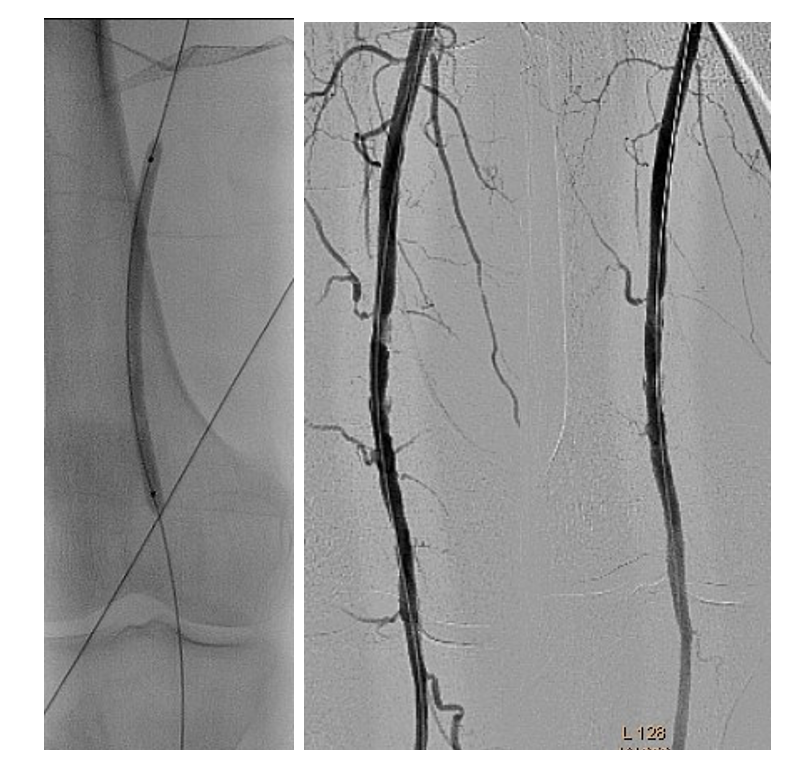

The angiography was performed via the left common femoral artery. The diagnostic catheterization of the right upper limb showed a thrombus in the origin of the right brachial artery, second level of thrombosis in the brachial bifurcation into its ulnar and radial branches, and poor distal filling of the radial artery (Figure 1).

The diagnostic catheterization of the right lower extremity showed a “riding” thrombus at the bifurcation of the superficial femoral artery (SFA)/profunda femoris artery (PFA) and a long thrombotic occlusion starting from the middle segment of the SFA involving the popliteal artery and tibiofibular trunk (Figure 2). In the setting of simultaneous acute limb ischemia (ALI) of the right upper and lower limbs, we performed ad hoc concomitant percutaneous transluminal thrombectomy (PTA).

The same introducer was redirected with the tip in the right common femoral artery. PTA of the right SFA, PFA, and popliteal and posterior tibial arteries was performed. Recanalization with a 0.035" Stiff Glidewire (Terumo) and a NaviCross Support Catheter (Terumo). The “riding” thrombus at the SFA/PFA bifurcation then migrated distally and occluded the SFA and PFA (Figure 8). We began EVT from the proximal segment of the SFA, with the same 2.06 mm AngioJet Solent Omni catheter. EVT was performed in the middle segment of the SFA and the popliteal artery (Figure 9). Due to residual thrombosis in the distal segment of the SFA, a balloon dilatation with a 5/120 mm Armada catheter (Abbott) was done (Figure 10).